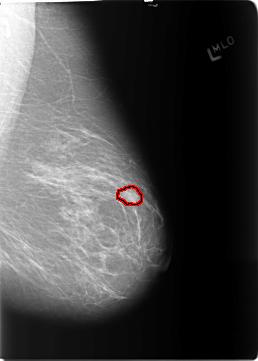

B_3122_1.LEFT_MLO

FILE: B_3122_1.LEFT_MLO.OVERLAY

TOTAL_ABNORMALITIES 1

ABNORMALITY 1

LESION_TYPE MASS SHAPE OVAL MARGINS ILL_DEFINED

ASSESSMENT 3

SUBTLETY 3

PATHOLOGY BENIGN

TOTAL_OUTLINES 1

BOUNDARY